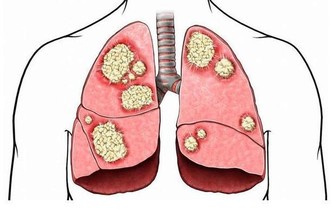

既不能懶惰,也不能勞累,這看似很矛盾,但其實只要掌握好度就能實現這些。中年人肩負著工作和家庭的重擔,承受的壓力也有限,如果超過了限度,那麼就會積勞成疾,容易生病。所以,中年人別太讓自己累著了。